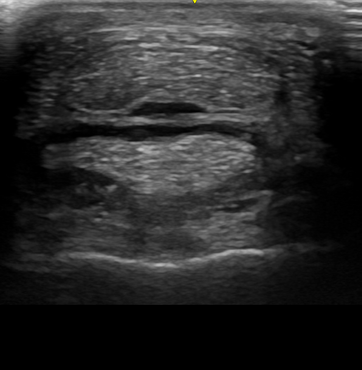

• Ultraschall zur hochauflösenden Beurteilung von Sehnen, Bändern und Gelenksstrukturen